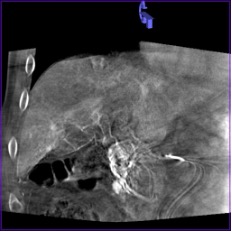

Высокое пространственное разрешение является ключевой сильной стороной ПДКТ, благодаря которой достигается четкая визуализация сосудов диаметром 250–300 мкм (0,25-0,30 мм) при проведении ПДКТ-артериографии (рис. 1). Такое высокое разрешение ПДКТ позволяет осуществлять прецизионный 3D-контроль установки стентов, микрокатетеров, тонких пункционных игл и других устройств непосредственно в рентгеноперационной (рис. 2). Пространственное разрешение характеризует точность воспроизведения малых структур в изоцентре и зависит от ряда факторов, таких как шаг пикселя, площадь сцинтиллятора, размер фокального пятна, геометрическое увеличение, стабильность системы во время сканирования, а также используемых фильтров реконструкции. Как уже было отмечено, применяемые в настоящее время a-Si:H/CsI:Tl ПДКТ-детекторы имеют высокие частотно-контрастные характеристики, благодаря конусовидному направлению света к каждому фотодиоду. Более толстый слой CsI улучшает поглощение, но увеличивает боковое размытие, снижающее контрастность, поэтому толщина и размер пикселя оптимизируются совместно [3, 4]. Пространственное разрешение напрямую зависит от режима считывания данных: при объединении (биннинге) пикселей, направленном на снижение шума и повышение контрастности получаемых изображений, пространственное разрешение прогрессивно снижается [35]. Как было показано в исследованиях на фантомах, ангиографическая установка Artis zee (Siemens Healthineers, Германия) при функции передачи модуляции (modulation transfer functions, MTF) в 10% достигает пространственного разрешения в 3,0 lp/mm при нативном считывании (1×1) и 1,5 lp/mm при биннинге 2×2, что превосходит разрешающую способность МСКТ (1,2–1,4 lp/mm в режимах высокого разрешения) [1, 35]. При использовании всех пикселей без их объединения разрешение может достигать почти 4,0 lp/mm, что соответствует возможности распознавания высококонтрастных деталей толщиной 130 мкм (0,13 мм) [35]. Переход на биннинг 2×2 удваивает размер эффективного пикселя с 154 мкм до 308 мкм, снижая MTF 10% вдвое, но повышая кадровую частоту до 30 кадров в секунду и минимизируя шум. При биннинге 4×4 (размер эффективного пикселя 616 мкм) разрешение падает до 1,0 lp/mm, однако возросшая скорость съёмки (60 кадров в секунду) и большее число проекций сокращает артефакты движения и улучшает контрастное разрешение, что чаще всего используется при визуализации органов брюшной полости и малого таза [35].

Рис. 1 (а-г). Церебральная ПДКТ-артериография бассейна правой общей сонной артерии, демонстрирующая возможность визуализации артерий диаметром 0,5 мм

Рис. 1а. Реконструкция всего артериального русла после проведения ПДКТ в режиме 20sDCT Head (Siemens Healthineers, Германия) с введением 60 мл контрастного препарата со скоростью 2 мл/с (в течение 30 с) и задержкой сканирования 10 с

Рис. 1б. Визуализация правой центральной артерии сетчатки глаза диаметром 0,5 мм в режиме MIP (тонкие срезы) у того же пациента

Рис. 1в-г. Визуализация той же артерии и дренирующих вен в косых проекциях (MIP) с использованием более толстых срезов.